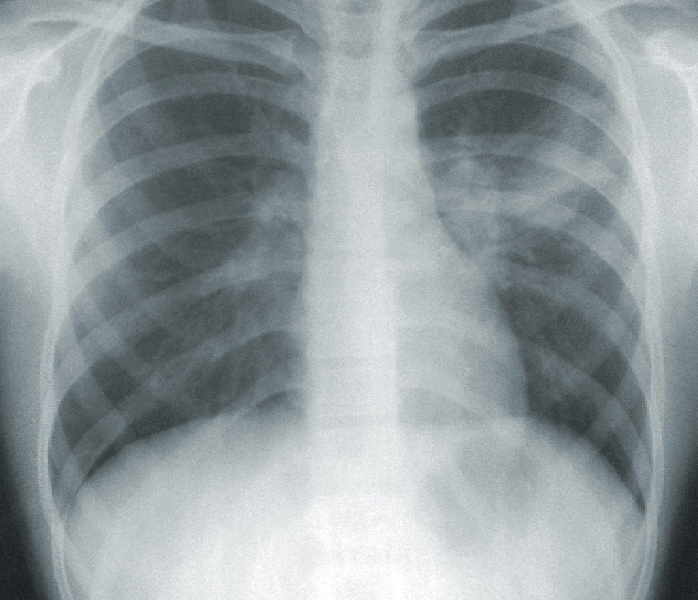

Lungebetændelse, også kendt som pneumoni, er en infektion i lungerne forårsaget af bakterier, vira eller svampe. Denne infektion skaber betændelse i lungevævet, hvilket kan gøre det svært for lungerne at udføre deres normale funktion – nemlig at optage ilt og udskille kuldioxid.

Lungebetændelse kan præsentere sig med en række symptomer, herunder hoste, feber, åndenød, brystsmerter, træthed og i nogle tilfælde slimproduktion (sputum). Symptomerne varierer i sværhedsgrad alt efter hvilken type mikroorganisme der er årsag til infektionen, samt personens individuelle immunrespons.

Der findes forskellige former for lungebetændelse. Den mest almindelige er samfundserhvervet lungebetændelse, som opstår uden for hospitalsmiljøer. En anden form er hospitalserhvervet lungebetændelse, som udvikles efter indlæggelse og kan være mere alvorlig. Risikofaktorer for at udvikle lungebetændelse inkluderer høj eller lav alder (børn under 2 år og ældre over 65 år), rygning, svækket immunforsvar, kroniske lungesygdomme og visse medicinske tilstande.

Behandlingen afhænger af årsagen og sværhedsgraden. Ved bakterielle infektioner anvendes antibiotika, mens virusinfektioner kan kræve antivirale midler. I tilfælde af svampeinfektioner benyttes svampedræbende medicin. Derudover er symptomlindrende behandling vigtig – det kan være hvile, væskeindtag og febernedsættende medicin for at støtte kroppen i helingsprocessen.

De fleste mennesker kommer sig helt uden mén, men gentagne lungebetændelser kan medføre nedsat bevægelighed i brystryggen, brystkassen og lungehinderne. Dette kan føre til en oplevelse af “stive lunger”, hvor vejrtrækningen føles besværet. I sådanne tilfælde kan vi hjælpe dig med osteopatisk behandling. Læs mere om stive lunger senere.